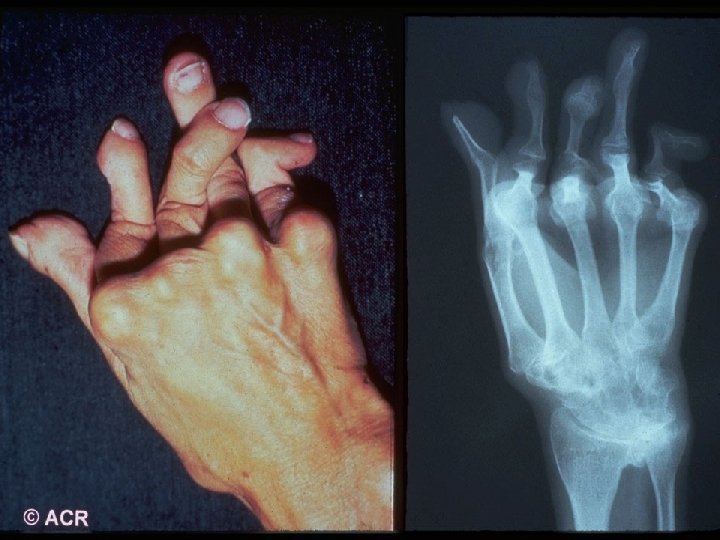

Rheumatoid Arthritis - A systemic, inflammatory polyarthritis that leads to joint destruction, deformity, and loss of function - Several potentially severe extra-articular manifestations - Pathology of RA involves the synovial membranes and periarticular structures of multiple joints, resulting in: - Pain - Swelling - Stiffness - Uncontrolled inflammation that can lead to irreversible damage and deformity - Functional limitation ACR Subcommittee on RA Guidelines. Arthritis Rheum. 2002; 46: 328– 346; Goronzy JJ, Weyand CM. In: Klippel JH, et al, eds. Primer on the Rheumatic Diseases. 12 th ed. Atlanta, GA: Arthritis Foundation; 2001: 209– 217; Anderson I. 2 RJ. ibid. 218– 225; Arnett FC, et al. Arthritis Rheum. 1988; 31: 315– 324.

ACR 1987 Classification Criteria For Rheumatoid Arthritis Patients Must have Four of Seven Criteria Morning Stiffness Lasting at Least 1 Hour* Swelling in 3 or More Joints* Swelling in Hand Joints* Symmetric Joint Swelling* Erosions or Decalcification on X-Ray of Hand Rheumatoid Nodules Abnormal Serum Rheumatoid Factor * Must Be Present at Least 6 Weeks

Baseline Evaluation of Patients · Physical Examination - Documentation of actively inflamed joints - Documentation of mechanical joint problems: loss of motion, crepitus, instability, deformity - Documentation of extra-articular manifestations - Optho, cardiac, pulmonary, rash, LAD

Sharp Scores of Radiographic Progression Erosion scores · 17 joints of each hand/wrist · 6 joints of each forefoot · Scale: 0– 5; Total score: 0– 230 Joint space narrowing (JSN) scores · 16 joints of each hand/wrist · 5 joints of each forefoot · Scale: 0– 4; Total score: 0– 168 Total Sharp score · Add erosion and JSN scores · Total score: 0– 398 Sharp JT, et al. Arthritis Rheum. 1985; 28: 1326– 1335 van der Heijde DM, et al. J Rheumatol. 1995; 22: 1792– 1796.

Prognostic Markers in RA · Definitive Markers - Subcutaneous nodules - Detection of erosions on x-ray

Joint Erosions Occur Early in RA Maximum % Joints Affected · Up to 93% of patients with <2 years of RA may have radiographic abnormalities · Erosions can be detected by MRI within 4 months of RA onset Hand MTP All · Rate of progression is significantly more rapid in the first year than in the second and third years Year Fuchs HA et al. J Rheumatol. 1989; 16: 585 -591. Mc. Queen FM et al. Ann Rheum Dis. 1998; 57: 350 -356. van der Heijde DM et al. J Rheumatol. 1995; 22: 1792 -1796.